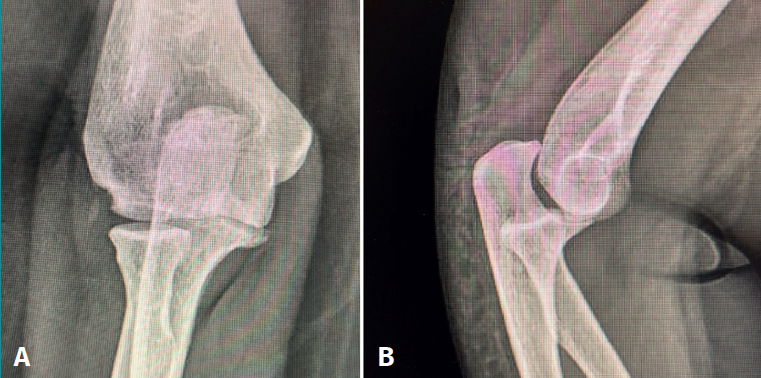

The patient was again evaluated in the clinic after 12 weeks. The physical examination revealed pain on the lateral aspect of the right elbow, with clicks on pronation, positive pivot shift manoeuvre and painful varus laxity. Complementary tests were requested: radiographs, which evidenced the Osborne-Cotterill lesion (Figure 1); a magnetic resonance imaging (MRI) scan showing distal deinsertion of the ulnar lateral collateral ligament and proximal deinsertion of the radial collateral ligament, as well as partial rupture of the annular ligament; and a computed tomography (CT) scan that found the Osborne-Cotterill osteochondral defect in the posterior capitellum to measure 8 × 3 mm (Figure 2). The patient suffered another posterior dislocation episode the following week after a new fall while undergoing rehabilitation. A second closed reduction was therefore performed.